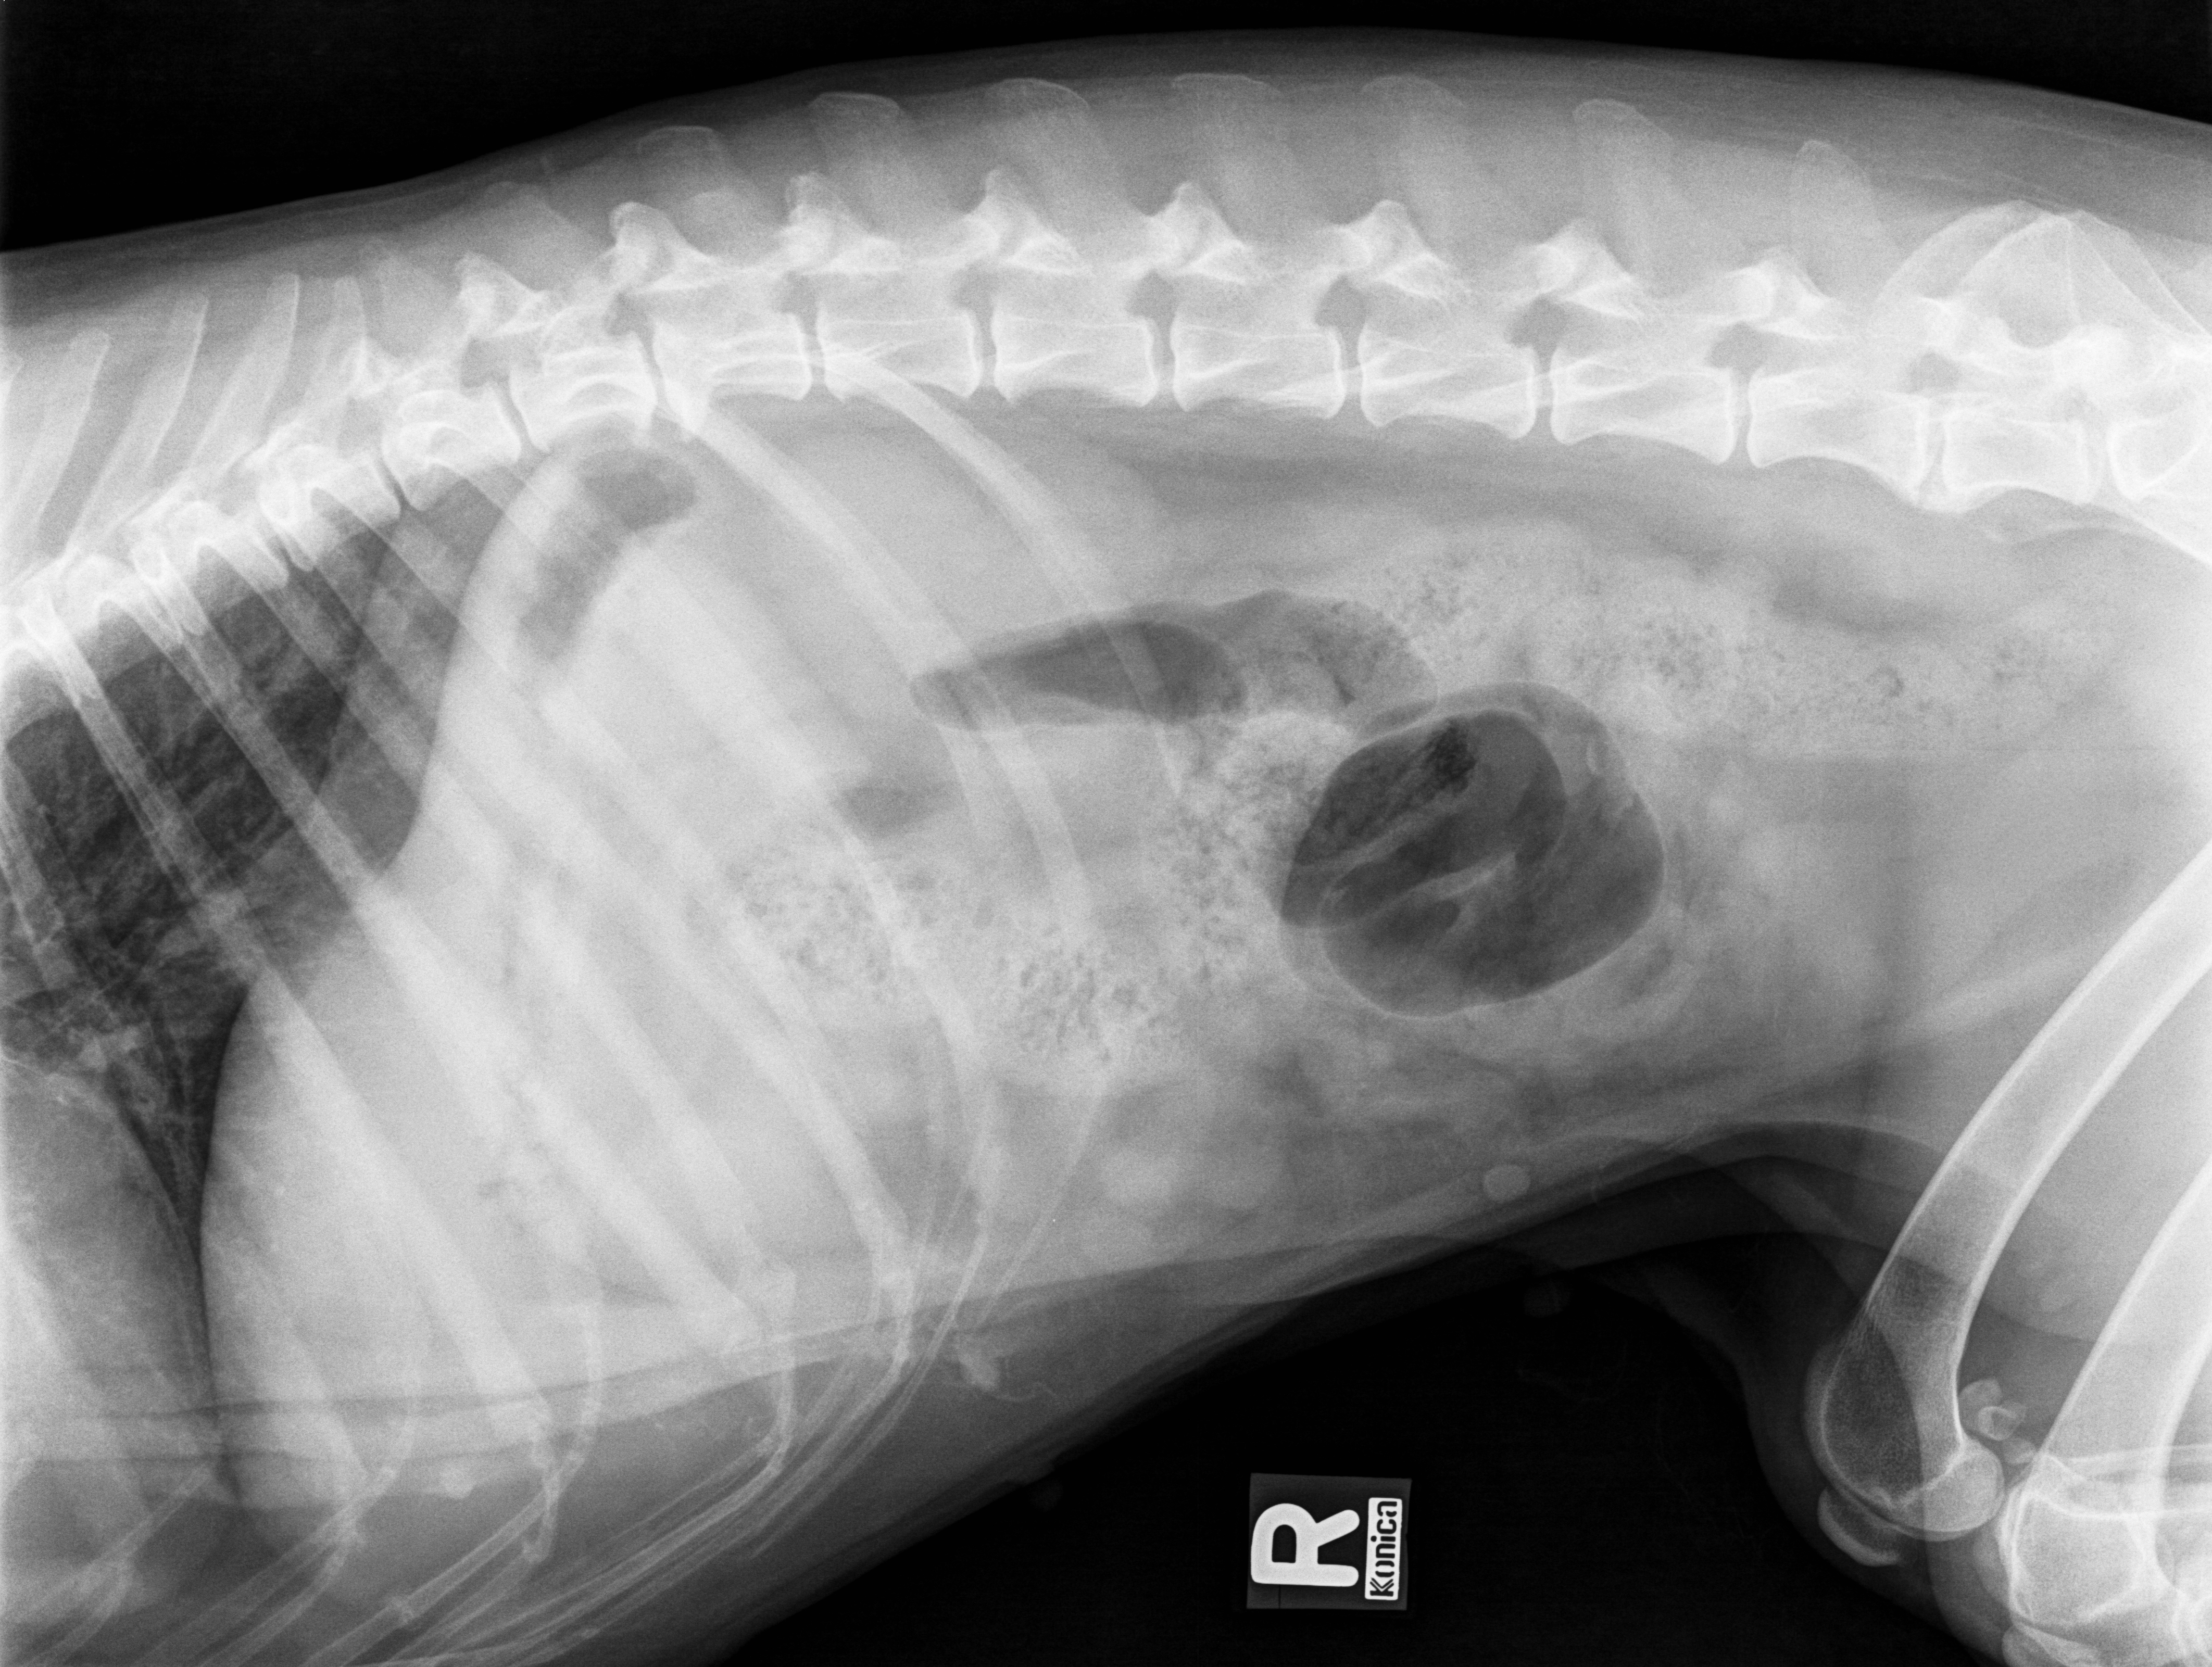

Latérale droite crâniale